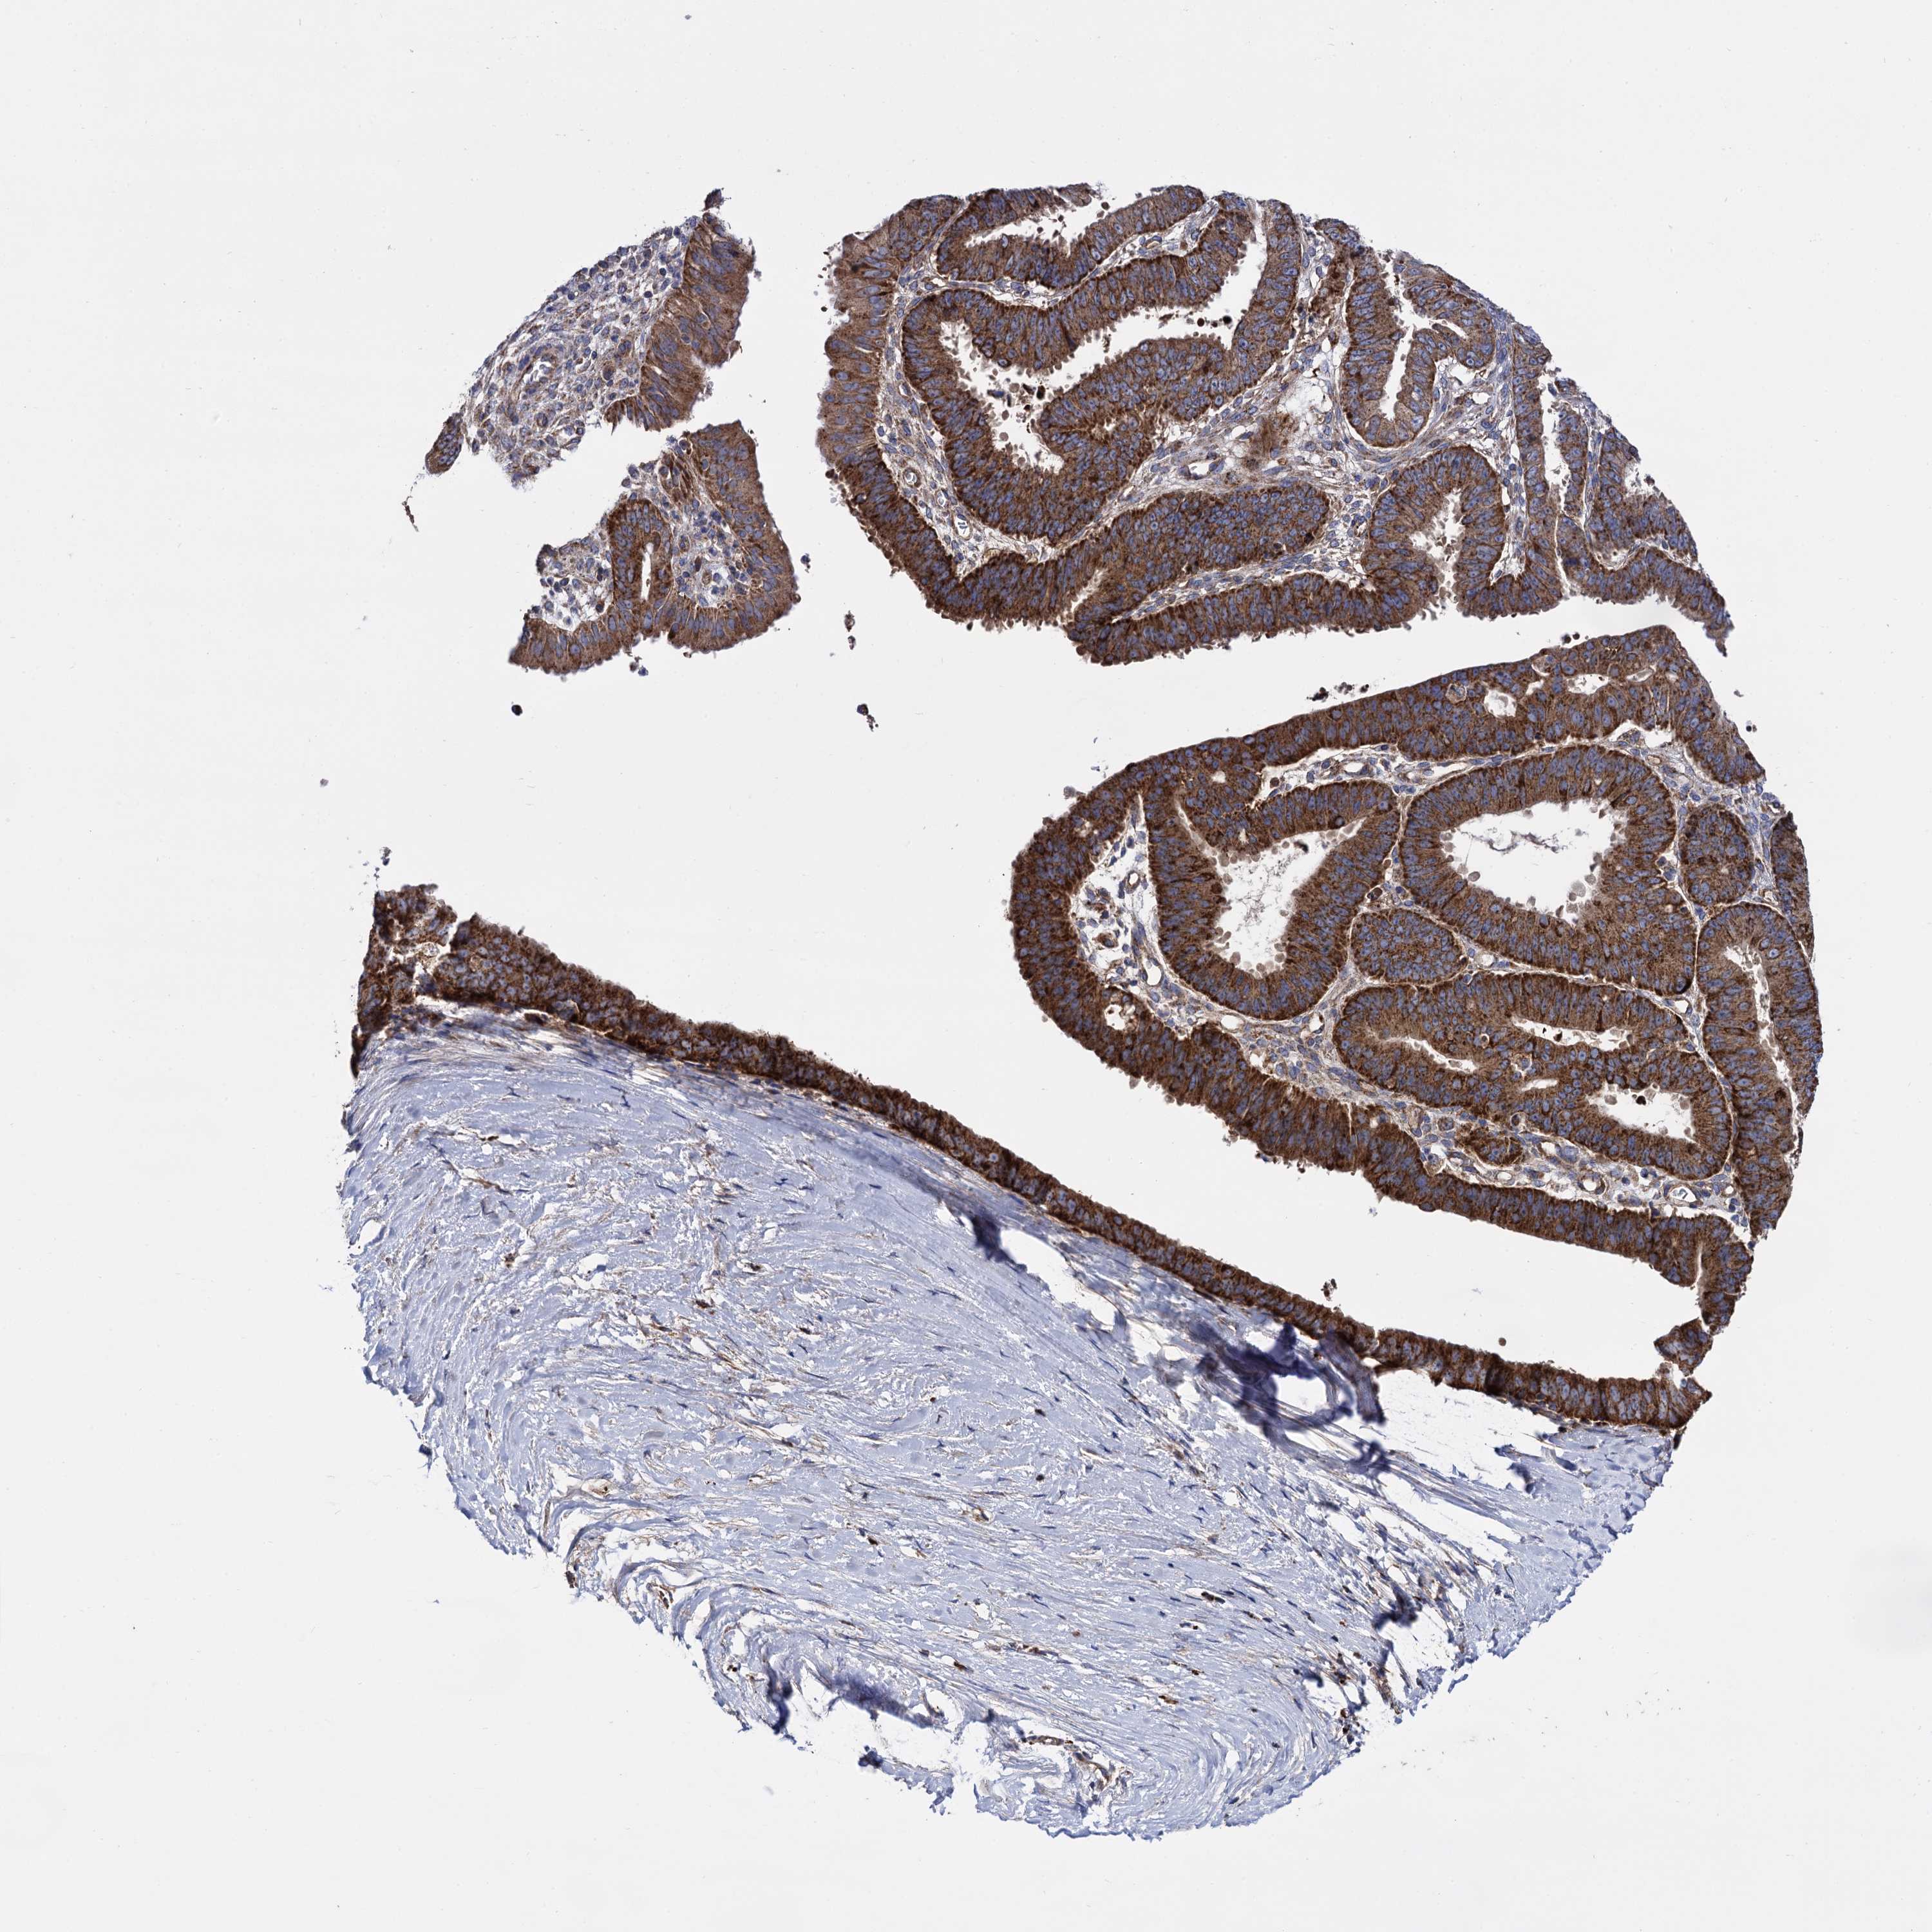

OVARIAN CANCER - Protein expressioni

A mouse-over function shows sample information and annotation data. Click on an image to view it in a full screen mode. Samples can be filtered based on level of antibody staining by selecting one or several of the following categories: high, medium, low and not detected. The assay and annotation is described here.

Note that samples used for immunohistochemistry by the Human Protein Atlas do not correspond to samples in the TCGA dataset.

Antibody stainingi

Antibody staining in the annotated cell types in the current human tissue is reported as not detected, low, medium, or high, based on conventional immunohistochemistry profiling in selected tissues. This score is based on the combination of the staining intensity and fraction of stained cells.

Each image is clickable and will lead to virtual microscopy that enables deeper exploration of all samples and also displays staining intensity scores, fraction scores and subcellular localization as well as patient and tissue information for each sample.

Antibody HPA040845

Staining

High

Medium

Low

Not detected

Intensity

Strong

Moderate

Weak

Negative

Quantity

>75%

75%-25%

<25%

None

Location

Nuclear

Cytoplasmic/membranous

Cytoplasmic/membranous,nuclear

Cystadenocarcinoma, serous, NOS

Carcinoma, endometroid

Cystadenocarcinoma, mucinous, NOS

Carcinoma, NOS